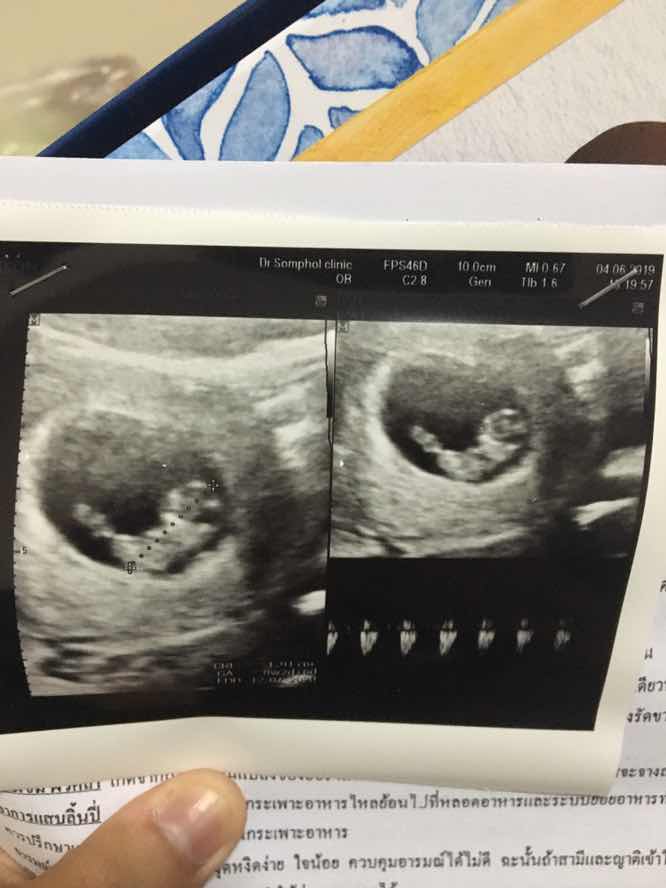

6w6d ซาวด์ผ่านหน้าท้อง พร้อมหัวใจเต้นตุ๊บๆ สู้ๆค่ะแม่ ใจเย็นๆค่ะ